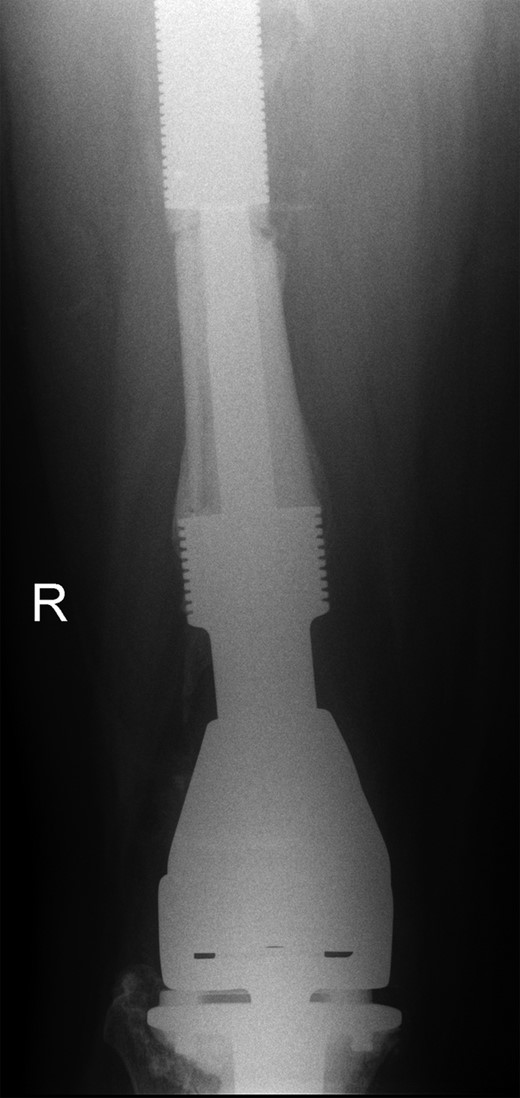

Retained proximal femoral component with new custom-made cement-linked distal femoral prosthesis visible in lower half of the image.

New custom-made distal femoral prosthesis cement-linked to original salvage proximal femoral component visible in upper half of the image.